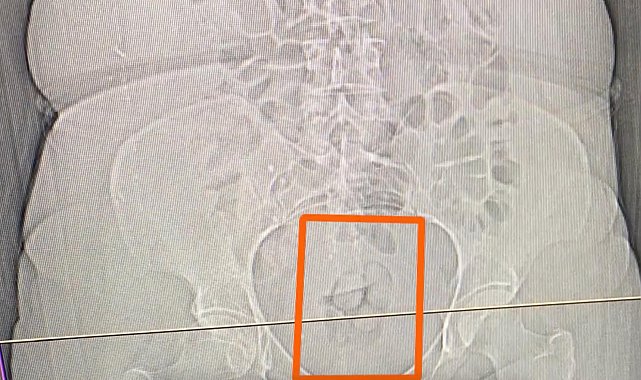

ERZİNCAN'da uyuşturucu ticareti yaptığı öne sürülen 4 şüpheli yakalanırken, içlerinden 1'inin midesinden 21,39 gram metamfetamin çıktı. İl Emniyet Müdürlüğü Narkotik Suçlarla Mücadele Şube Müdürlüğü ve İstihbarat Şube Müdürlüğü ekipleri, uyuşturucu madde ticareti yapan ve kullanan şüphelilere yönelik çalışma yaptı. Bu kapsamda F.U.C., R.B.C., Ö.K. ve S.S. isimli kişilerin Erzincan'a uyuşturucu madde getirileceği bilgisine ulaşıldı. Şüphelilerin içerisinde bulunduğu araç, takibe alınıp durduruldu. Araçta yapılan aramada 16,40 gram metamfetamin geçirildi. Gözaltına alınan 4 şüpheliden S.S.'nin şüpheli davranışları üzerine tomografi çekildi ve midesinde 21,39 gram metamfetamin olduğu tespit edildi. Uyuşturucu madde doğal yollarla çıkartılırken, adliyeye sevk edilen 4 şüpheli hakkında 'Uyuşturucu veya uyarıcı madde imal ve ticareti" suçundan işlem yapıldı.

Midesinden 21,39 gram metamfetamin çıktı

Muzaffer KOŞAN/ERZİNCAN, (DHA)- ERZİNCAN'da uyuşturucu ticareti yaptığı öne sürülen 4 şüpheli yakalanırken, içlerinden 1'inin midesinden 21,39 gram metamfetamin çıktı